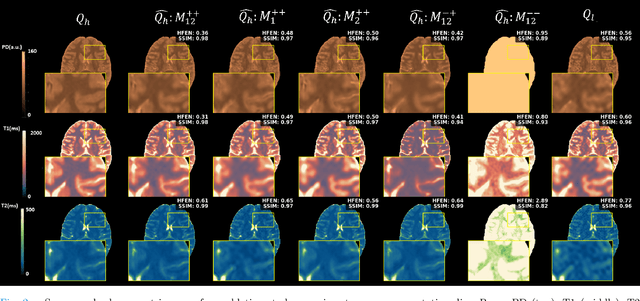

Abstract:High-resolution (HR) quantitative MRI (qMRI) relaxometry provides objective tissue characterization but remains clinically underutilized due to lengthy acquisition times. We propose a physics-informed, self-supervised framework for qMRI super-resolution that uses routinely acquired HR weighted MRI (wMRI) scans as guidance, thus, removing the necessity for HR qMRI ground truth during training. We formulate super-resolution as Bayesian maximum a posteriori inference, minimizing two discrepancies: (1) between HR images synthesized from super-resolved qMRI maps and acquired wMRI guides via forward signal models, and (2) between acquired LR qMRI and downsampled predictions. This physics-informed objective allows the models to learn from clinical wMRI without HR qMRI supervision. To validate the concept, we generate training data by synthesizing wMRI guides from HR qMRI using signal equations, then degrading qMRI resolution via k-space truncation. A deep neural network learns the super-resolution mapping. Ablation experiments demonstrate that T1-weighted images primarily enhance T1 maps, T2-weighted images improve T2 maps, and combined guidance optimally enhances all parameters simultaneously. Validation on independently acquired in-vivo data from a different qMRI sequence confirms cross-qMRI sequence generalizability. Models trained on synthetic data can produce super-resolved maps from a 1-minute acquisition with quality comparable to a 5-minute reference scan, leveraging the scanner-independent nature of relaxometry parameters. By decoupling training from HR qMRI requirement, our framework enables fast qMRI acquisitions enhanced via routine clinical images, offering a practical pathway for integrating quantitative relaxometry into clinical workflows with acceptable additional scan time.